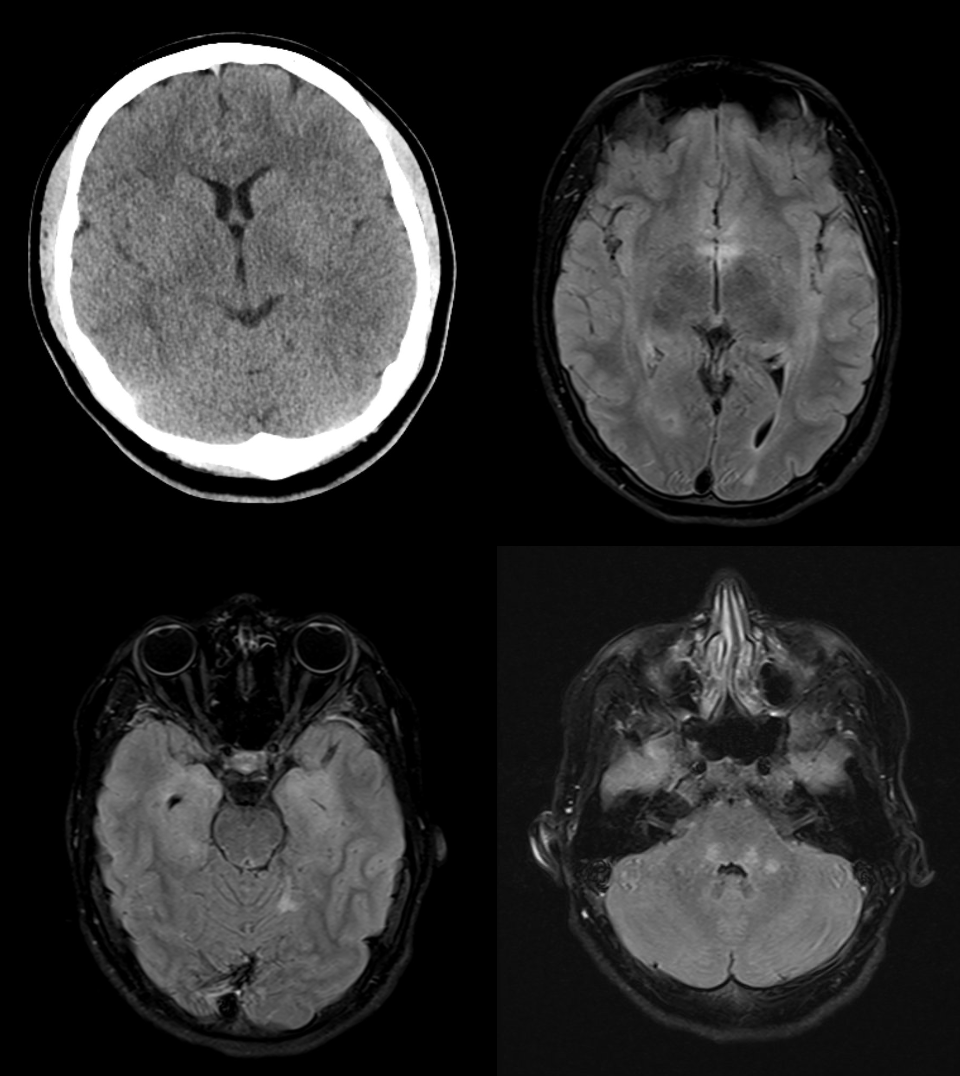

Abbildung 2: Verlaufskontrollen mittels MRT

A: Initiale Bildgebung. B: Verlaufskontrolle nach 10 Monaten. C: Verlaufskontrolle nach zwei Jahren.

Es zeigt sich eine deutliche Reduktion der T2w-Hyperintensitäten im Laufe der Zeit, was mit der klinischen Besserung korreliert.